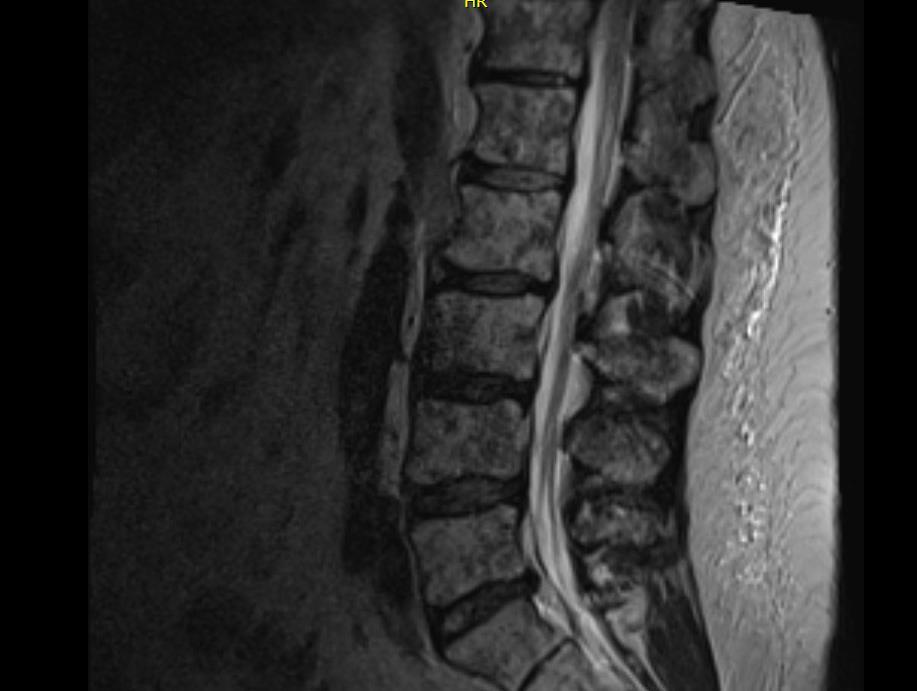

Margaret*

PATIENT NOTES:

• Academic center: High-risk SMM based on labs

• ECOG trial suggested (Rd ± Dara) → Screening

*HIPAA-compliant, not actual patient name or stock photo.

Whole Body PET-CT FDG-avid lesions T10-T12, lateral right ribs

Whole Spine MRI T10 to T12 lesions, intact spinal canal

FISH Gain(1q)

Diagnosis Active MM, R-ISS II

not actual patient name, stock photo.

CASE 1

30 CT = computed tomography; Dara = daratumumab; ECOG = Eastern Cooperative Oncology Group; FDG = fluorodeoxyglucose; FISH = fluorescence in situ hybridization; HIPAA = Health Insurance Portability and Accountability Act; MM = multiple myeloma; MRI = magnetic resonance imaging; PET = positron emission tomography; R-ISS = Revised International Staging System; Rd = lenalidomide dexamethasone; SMM = smoldering multiple myeloma.

Median Age at Diagnosis of MM Varies by Race/Ethnicity